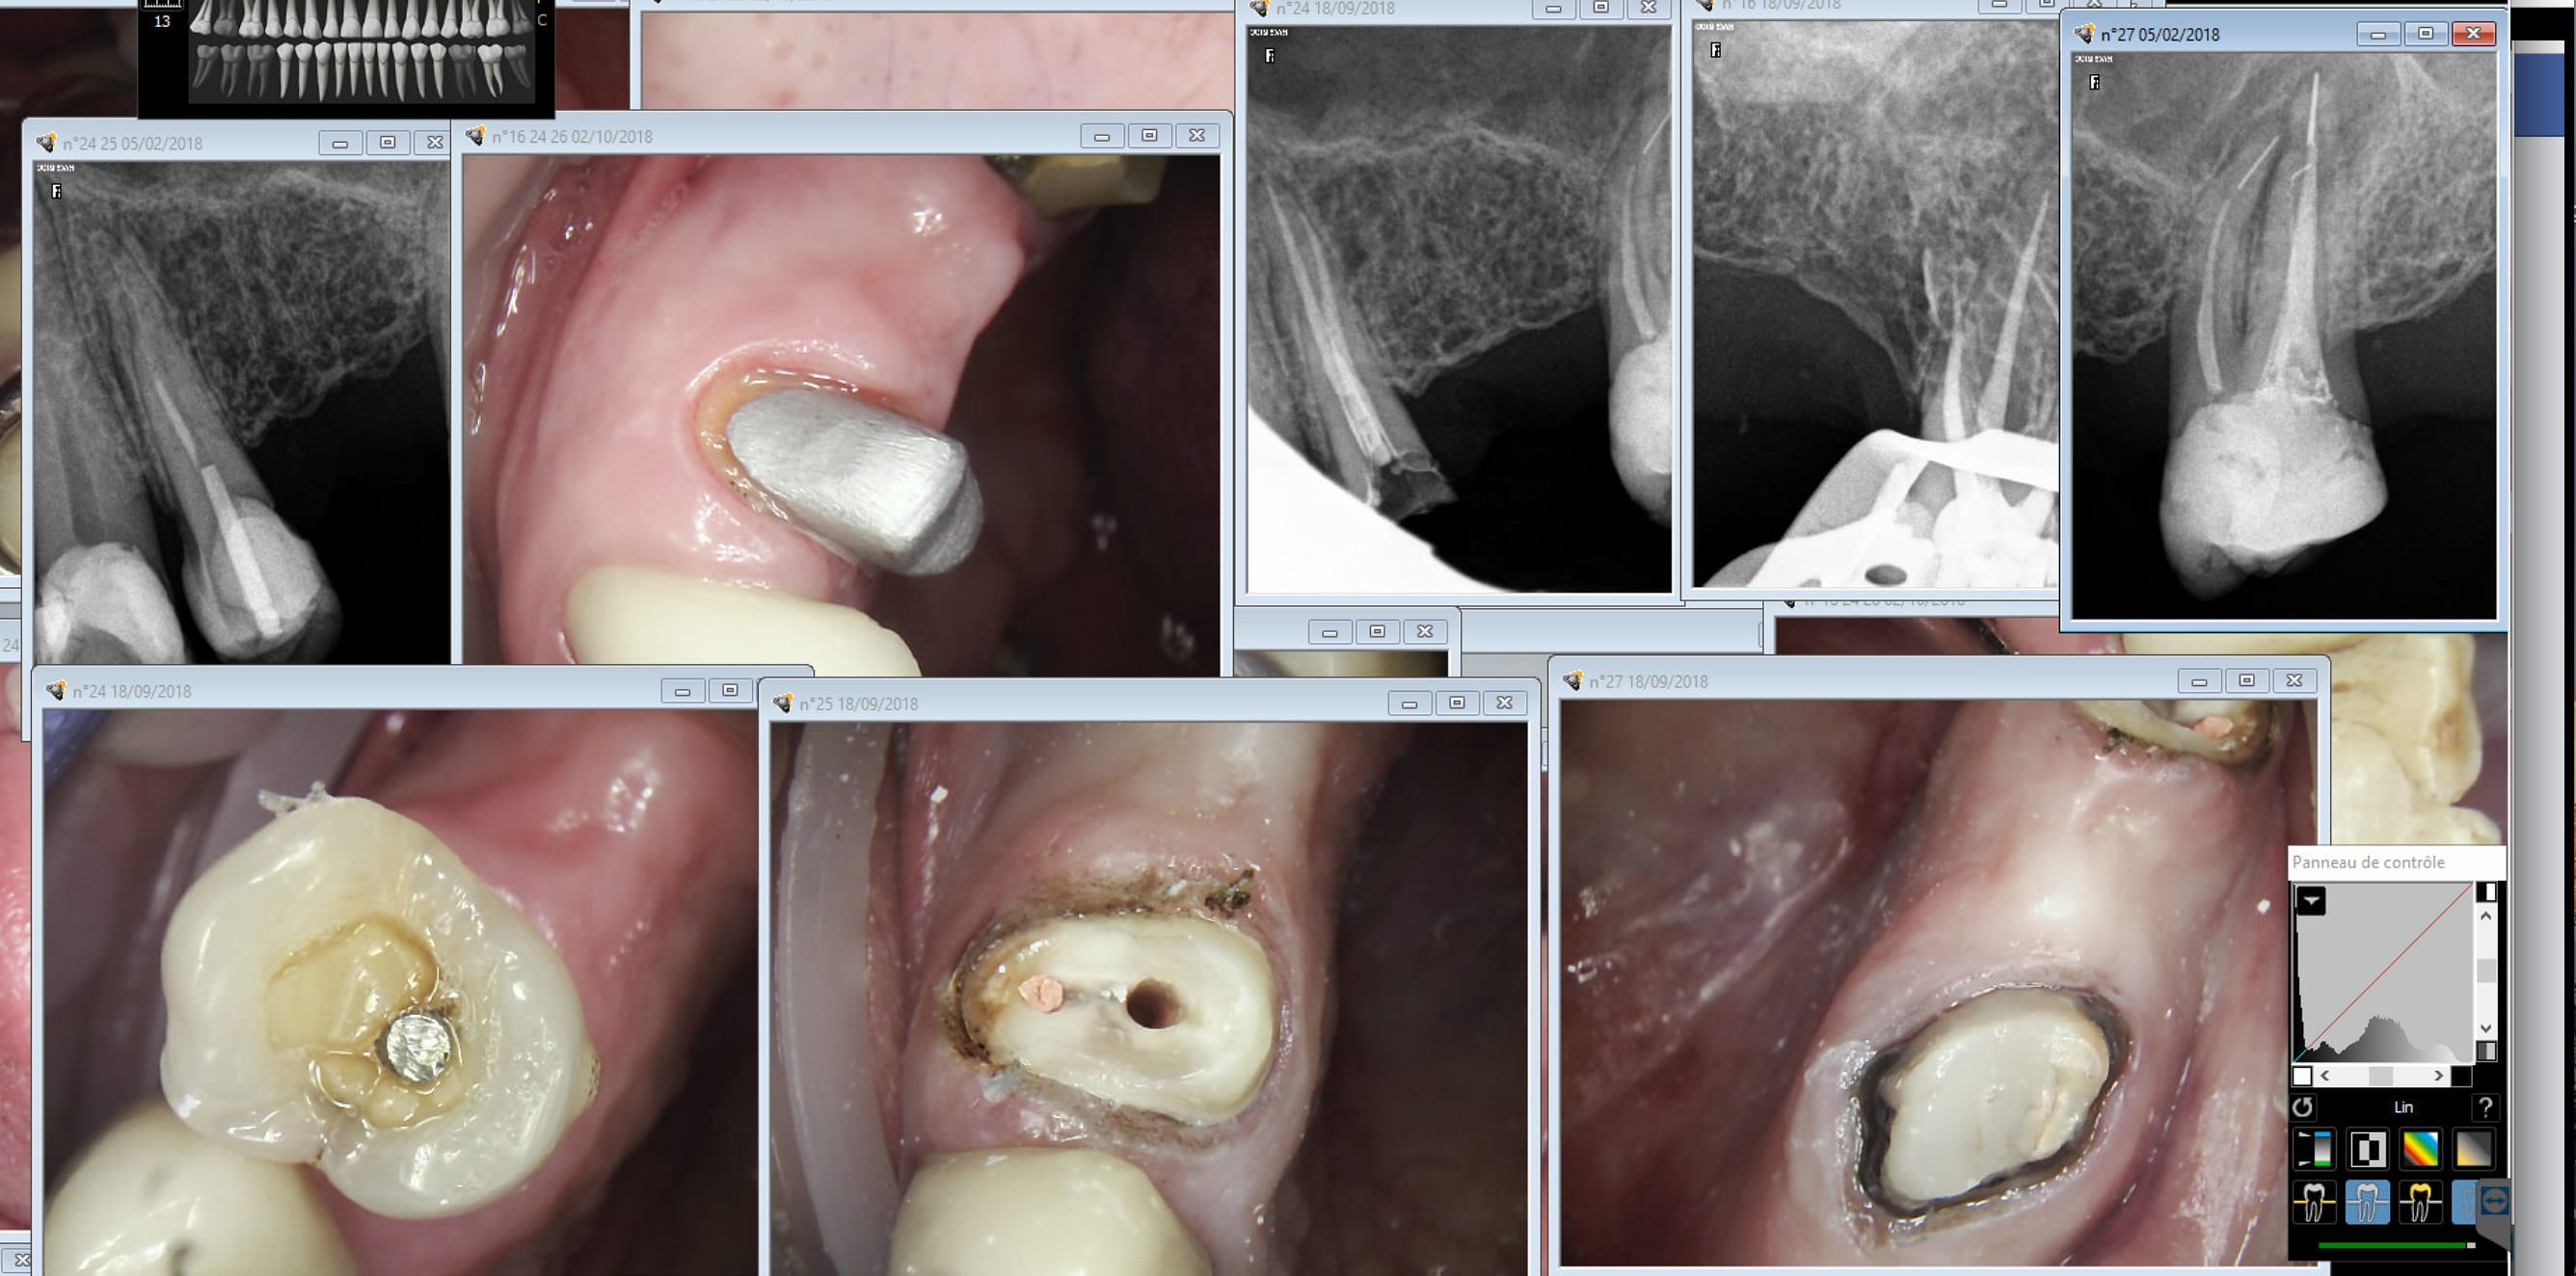

La 24 je l'ai récupérée . La 27 j'ai pas été jouer dans les canaux pour récupérer les instruments pétés. (Je suis nul en endo) . Premier endo exclusif 150 bornes .........CMU à moitié assidu c'était pas gagné. -))))

Ca c'était un CMU aussi. La prochaine fois je penserais à demander le stellite haut en plus de la couronne. Ca ouvre des perspectives intéressantes. 2 minutes de scannage en plus et pouf ! terminé. -)))